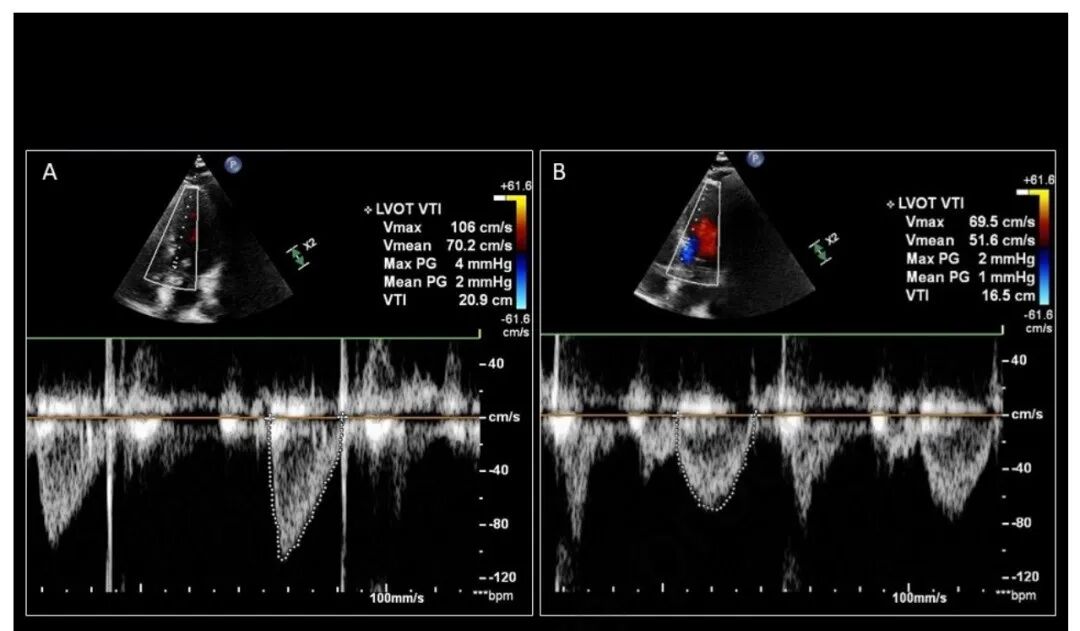

准确获取 LVOT VTI 跟踪非常重要。这要求 PW 多普勒采样线与 LVOT 内的血流平行。如果声波角度在 20° 以内,实际多普勒频移误差 ≤ 6%,导出的 SV 将是可靠的(图 4)。PW 采样点也需要放置在主动脉瓣近端,而不是 LV 腔本身内(图 5)。获得良好的 LVOT VTI 由内部“暗”和明亮“轮廓”的光谱包络表示。追踪 LVOT VTI 时,尽可能精确并尽可能接近外边缘非常重要(图 6)

动态 LVOT 梗阻,最常见的原因是二尖瓣的收缩期前向运动 (SAM),会干扰准确的 LVOT VTI 测量。在动态 LVOT 阻塞的情况下,血流速度通常超过奈奎斯特极限,导致称为混叠的现象。当超声机器无法确定穿过采样区域的血流的真实方向和速度时,就会出现混叠,并且由从基线的顶部到底部融合的光谱包络表示(图 7A)并且不能 可靠地追踪。在这种情况下,无法从 LVOT VTI 进行 SV 评估。大多数初学者可能只注意到动态 LVOT 梗阻时 LVOT VTI 存在混叠,但在 2D 成像中,重要的是评估二尖瓣叶置在收缩期间的前向运动(图 7B)。

图 7. 动态 LVOT 梗阻 (A) LVOT VTI 描述,以及 (B) 二尖瓣收缩期前运动 (SAM) 的 2D 可视化。(C) 中重度主动脉瓣反流中预期的彩色多普勒结果。

中度或重度主动脉瓣关闭不全

中度或重度主动脉瓣关闭不全 (AI) 导致左心房和主动脉的双源舒张期充盈。左心室舒张末期容积的增加导致超常的、高估的 LVOT VTI 值。由于这种高估,不能从 LVOT VTI 进行 SV 评估。即使是 CCE 的新手用户,也可以在彩色多普勒的 PLAX 和 A5c 视图中通过评估在舒张期从主动脉回流到 LV 的逆行血流(图 7C)来发现主动脉瓣关闭不全(图 7C)